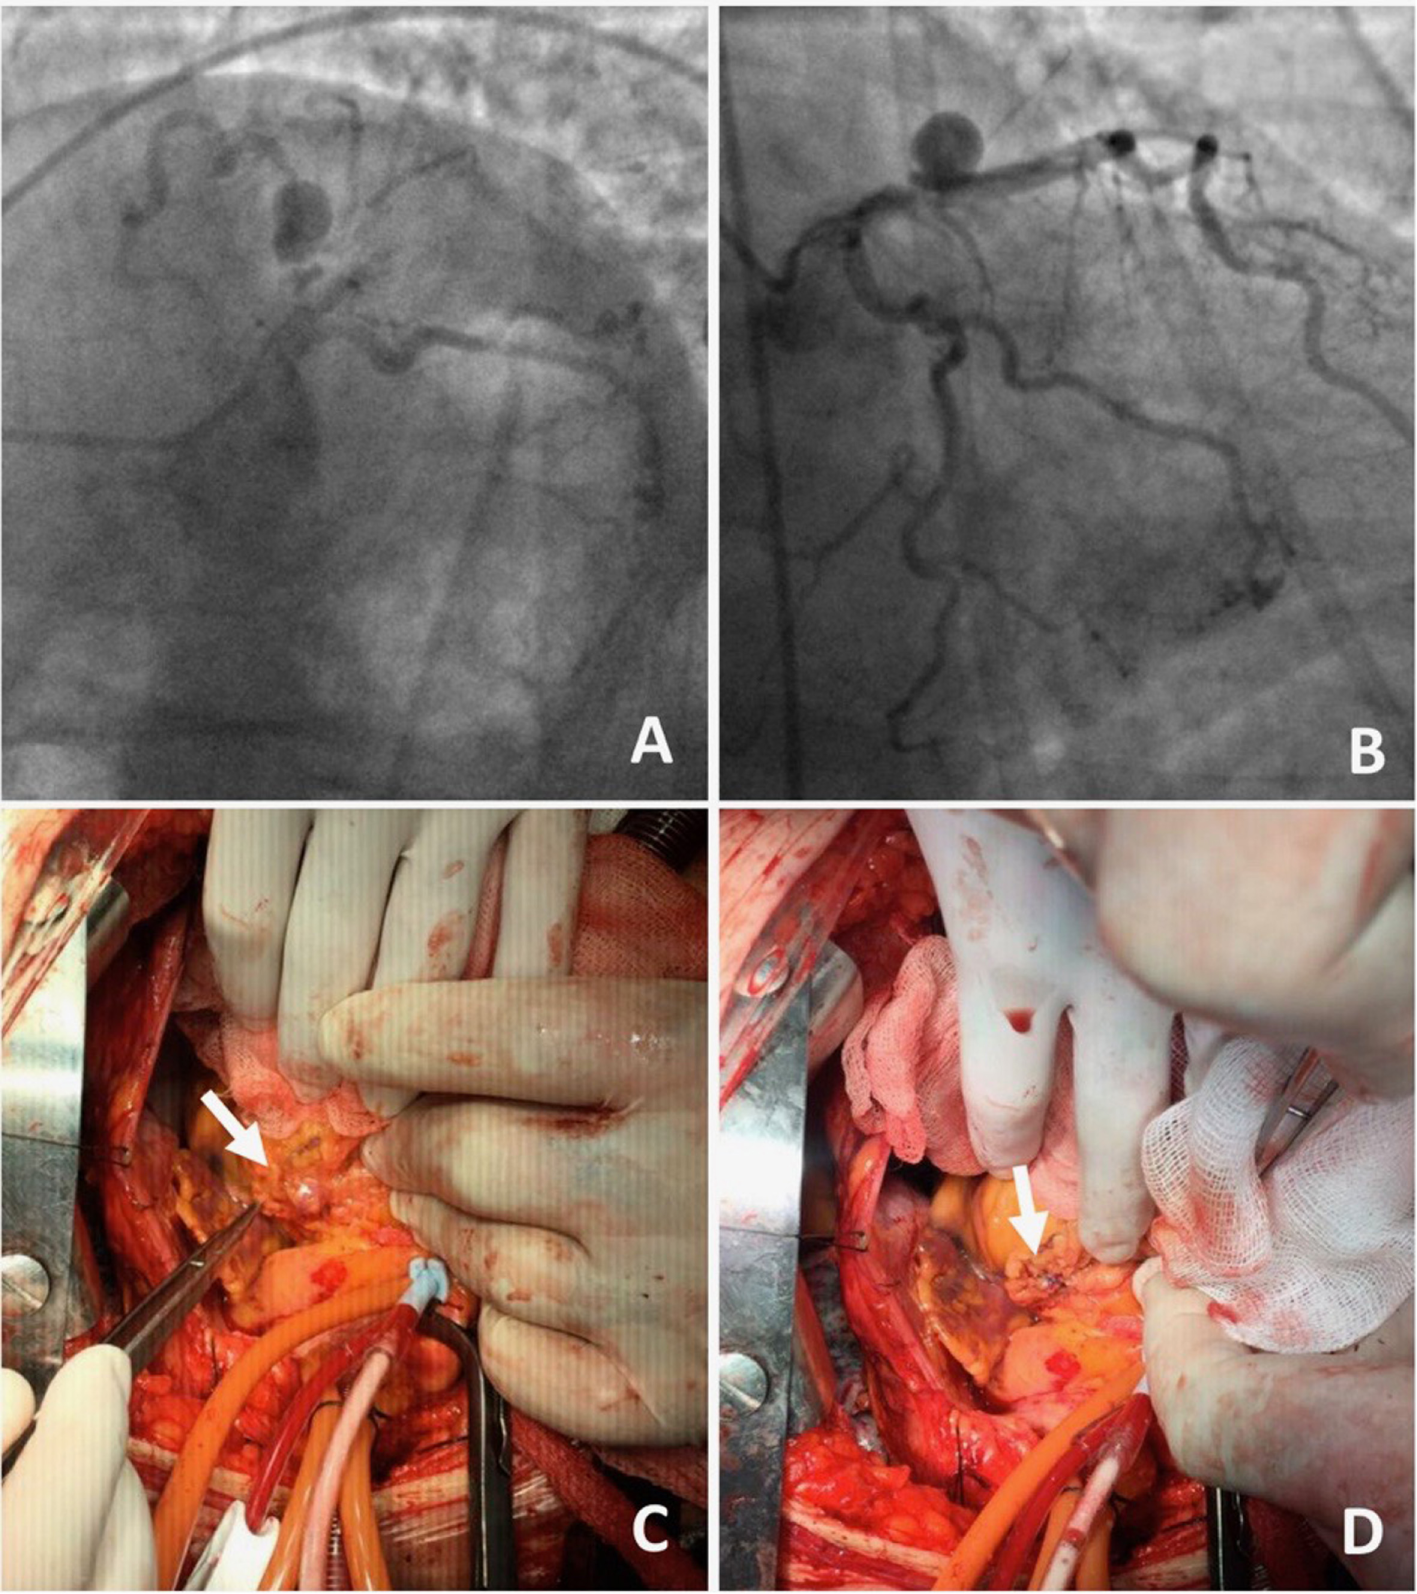

Figure 4

A 70-year-old male presented with angina on exertion. Three years prior to this presentation, they had an abdominal aortic aneurysm repair.(A,B) Coronary angiogram revealed coronary artery disease and an aneurysm in the left anterior descending artery. The patient was referred to surgery, because of the risk of occlusion of the significant side branches, if a stent was to be used. (C,D) Coronary aneurysm was surgically excluded with a linear repair (images courtesy of Yalin Tolga Yaylali and Bilgin Emrecan).